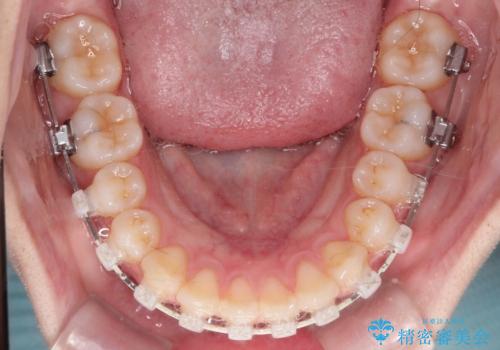

上と下の前歯がずれているため、抜歯を行い前歯の真ん中を合わせる治療計画を立ててワイヤー矯正にて治療を行いました。

途中、矯正用のアンカースクリューを使うことで、最終的にきれいに前歯の真ん中を合わせることができました。

矯正用アンカースクリューを使用することで、歯の移動量をコントロールできるため、治療の仕上がりをよくすることができます。